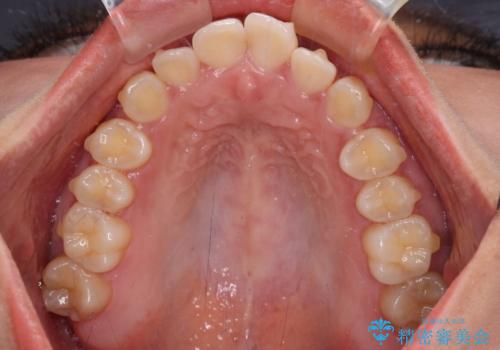

治療途中に上顎前歯が歯髄壊死を起こし、変色してしまいました。

痛みを感じたらすぐに連絡いただくよう伝えていましたが、忘れてしまっており、痛みと変色が発現したことで、すぐに連絡することを思い出されたとのことでした。

今後は、根管治療を行った後に、オールセラミッククラウンにて補綴治療を行う予定です。